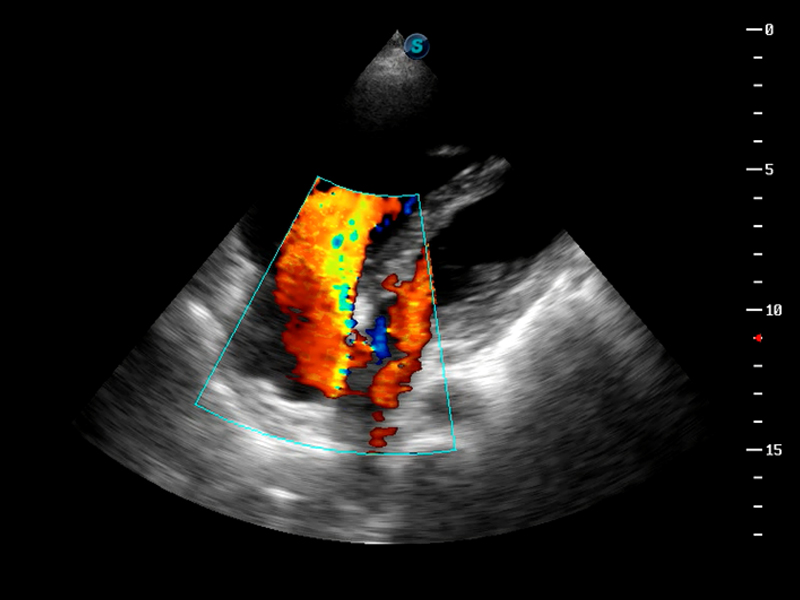

成像技术

TDI组织多普勒成像